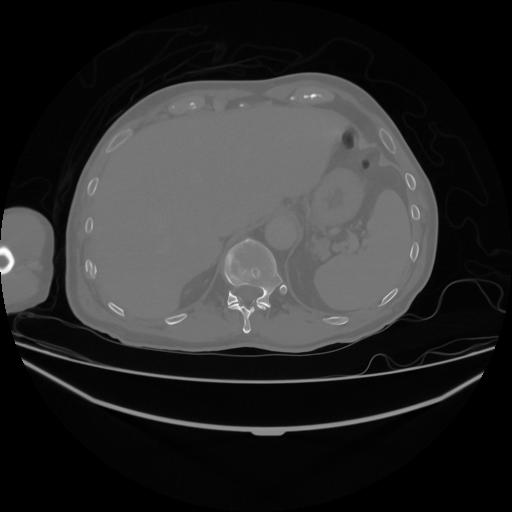

5 CUERPO,CE,Vol,1.0,CUERPO,,